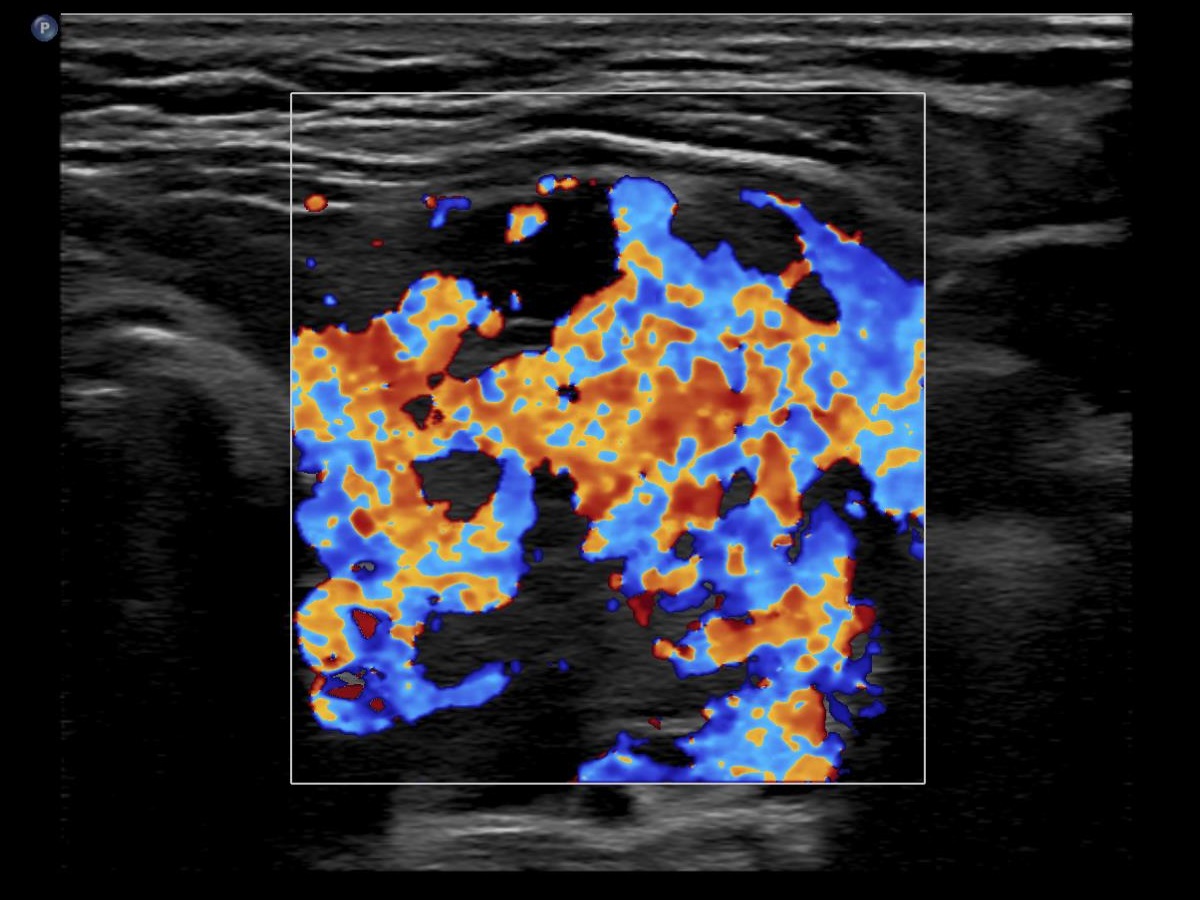

Graves' disease - case 2151

One year after the first examination (ultrasonographic picture 7)

Right lobe, longitudinal scan

Left lobe, transverse scan, color Doppler mode. The vascularization is extermely increased.